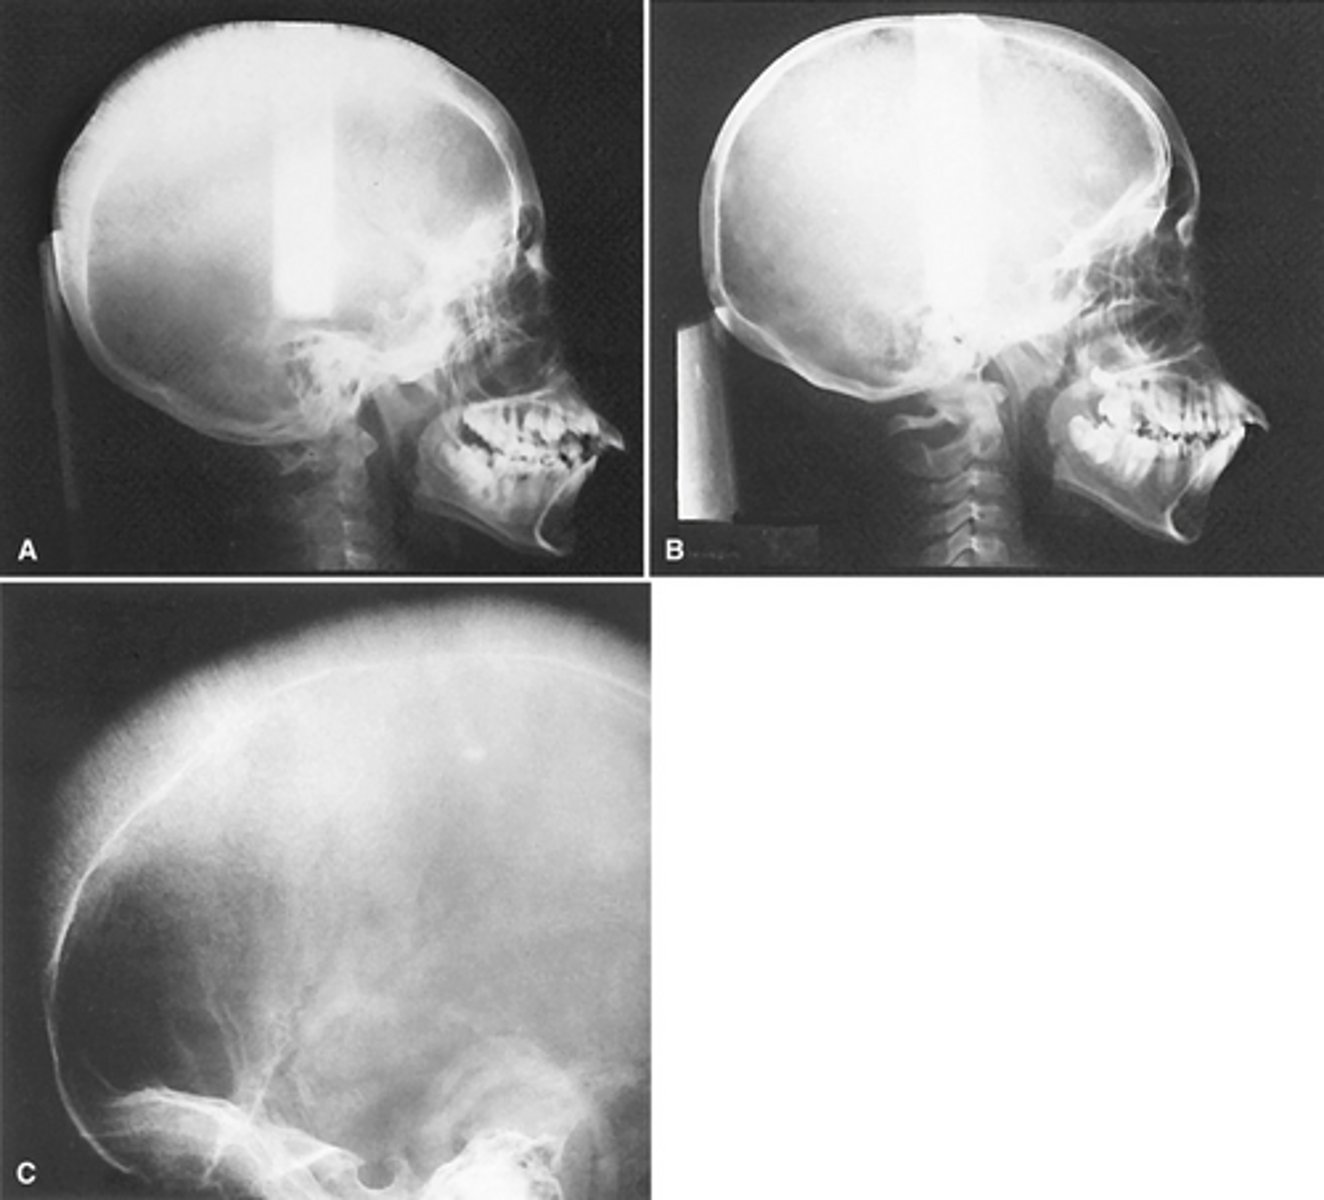

Image A shows a lateral ceph where the patient has a steep mandibular plane and anterior open bite.

Image B shows erosion of the temporal component of the TMJ

What is the diagnosis of the patient based off these radiographs and what are the features?

Monostotic Fibrous Dysplasia- (a) earlier more radiolucent stage. (b) 18 years later more radiopaque stage

images showing a simple bone cyst developing within a focus of fibrous dysplasia